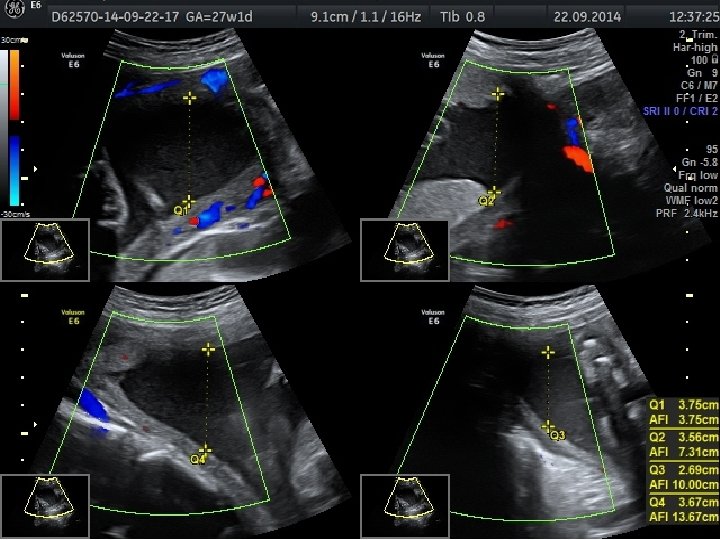

FETAL BÜYÜME BOZUKLUKLARINDA TAKİP VE DOĞUM • Günlük pratikte gelişme gerilikli fetusların takibi, ultrasonografi ile fetal biyometri ve amniyotik sıvı miktarının belirli aralıklarla ölçülmesi ile ve nonstres test veya biyofizik profil gibi antepartum fetal iyilik hali testleri ile yapılmaktadır. • Plasental yetmezliğe bağlı gelişen fetal gelişme geriliğinde standart fetal izlem ile birlikte fetal arterial/venöz dolaşımın Doppler değerlendirmesinin nonstres test ve biyofizik profili ile birlikte kullanımının daha iyi fetal sonuçlar ile ilişkili olduğu gösterilmiştir.

Obstetrik Doppler Ultrasonografi • Umblikal arter Doppler’i en yaygın olarak kullanılan fetal Doppler değerlendirmesidir ve en fazla kullanılan Doppler parametresidir. • Orta serberal arter Doppler • Umblikal arter Doppler değerlendirmesinde direnç artışı, diyastol sonu akımda kayıp veya ters dönme saptanması , artmış perinatal mortalite hızı ile ilişkili olmakla birlikte fetal gelişme geriliği olgularında doğum zamanlamasının belirlenmesini de etkilemektedir.

• Duktus venosus Doppler’inin kötü perinatal sonuçları tahmin etmedeki katkısı sınırlı olmakla birlikte yenidoğan sonuçlarını öngörmede en önemli kardiyovasküler parametre duktus venosus Doppler’idir.